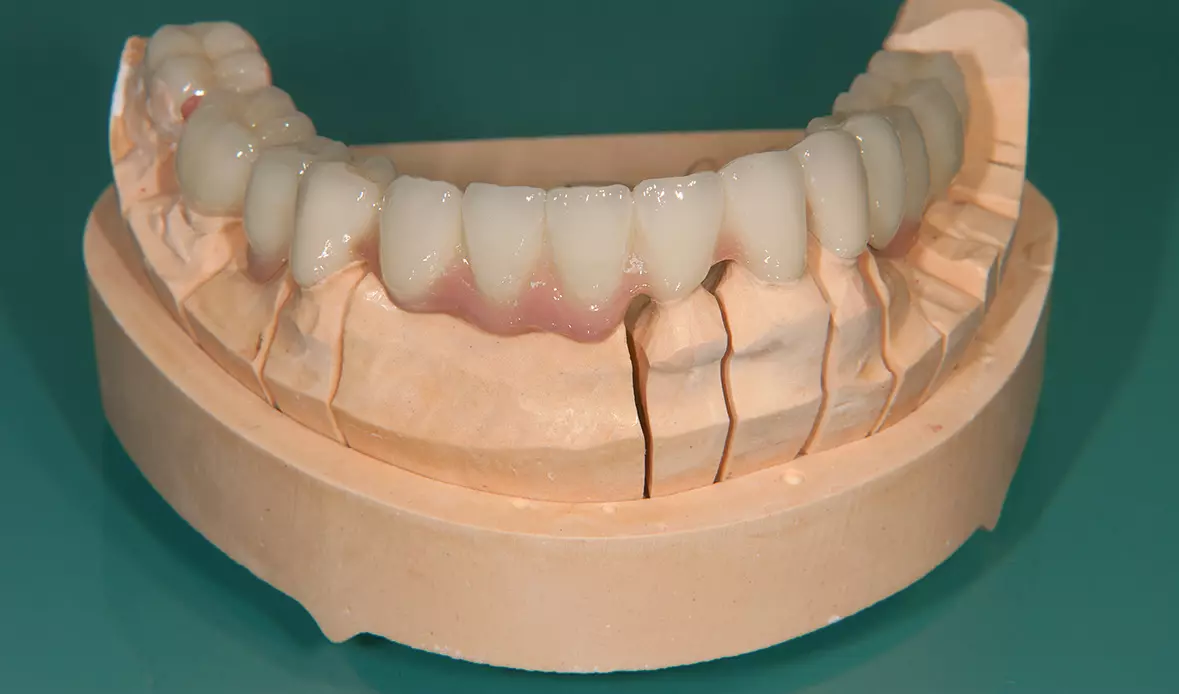

Abb. 29: Fertige Brücken im Unterkiefer. Dr. Michael Leistner

Abb. 29: Fertige Brücken im Unterkiefer.

Abb. 30: Fertige Brücken im Unterkiefer von lingual. Dr. Michael Leistner

Abb. 30: Fertige Brücken im Unterkiefer von lingual.